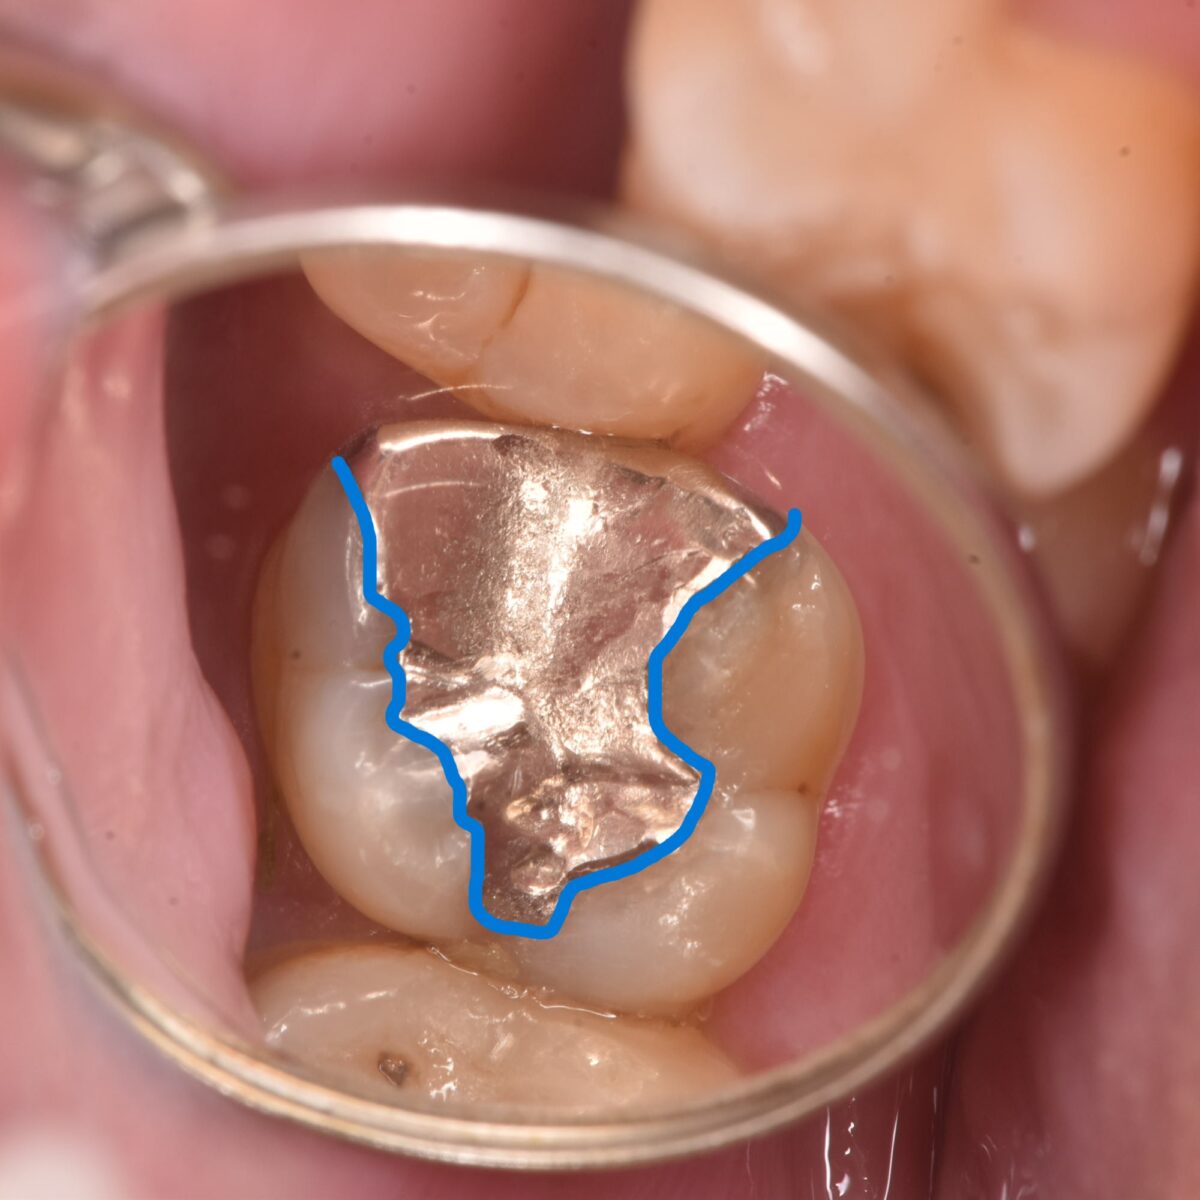

時間の経った銀歯の治療

【東京メトロ東西線妙典駅 徒歩5分の歯医者】市川、妙典の歯科医院、めぐりデンタルクリニックの梶原です。 銀歯の治療について、今までも何度か書いてきましたが、今回も内容的には重複しま…